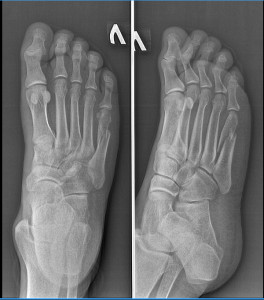

Добрый день. Получил перелом 5 плюсневой кости 18.12.2025, посоветуйте что тут лучше делать, либо ставить пластину либо  гипс без операции. Спасибо

Здравствуйте. По снимкам перелом 5-й плюсневой выглядит без значимого смещения. В таких случаях чаще выбирают консервативное лечение т.е иммобилизацию гипсом или ортезом и нагрузку с ограничением на 4-6 недель. Операция с пластиной обычно нужна только при выраженном смещении, нестабильности или угрожающих условиях для правильного срастания. Вашему травматологу виднее по очной оценке, но по рентгену показаний к обязательной фиксации пластиной не видно.